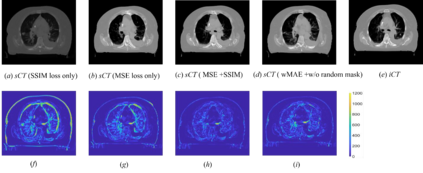

Purpose: In some proton therapy facilities, patient alignment relies on two 2D orthogonal kV images, taken at fixed, oblique angles, as no 3D on-the-bed imaging is available. The visibility of the tumor in kV images is limited since the patient's 3D anatomy is projected onto a 2D plane, especially when the tumor is behind high-density structures such as bones. This can lead to large patient setup errors. A solution is to reconstruct the 3D CT image from the kV images obtained at the treatment isocenter in the treatment position. Methods: An asymmetric autoencoder-like network built with vision-transformer blocks was developed. The data was collected from 1 head and neck patient: 2 orthogonal kV images (1024x1024 voxels), 1 3D CT with padding (512x512x512) acquired from the in-room CT-on-rails before kVs were taken and 2 digitally-reconstructed-radiograph (DRR) images (512x512) based on the CT. We resampled kV images every 8 voxels and DRR and CT every 4 voxels, thus formed a dataset consisting of 262,144 samples, in which the images have a dimension of 128 for each direction. In training, both kV and DRR images were utilized, and the encoder was encouraged to learn the jointed feature map from both kV and DRR images. In testing, only independent kV images were used. The full-size synthetic CT (sCT) was achieved by concatenating the sCTs generated by the model according to their spatial information. The image quality of the synthetic CT (sCT) was evaluated using mean absolute error (MAE) and per-voxel-absolute-CT-number-difference volume histogram (CDVH). Results: The model achieved a speed of 2.1s and a MAE of <40HU. The CDVH showed that <5% of the voxels had a per-voxel-absolute-CT-number-difference larger than 185 HU. Conclusion: A patient-specific vision-transformer-based network was developed and shown to be accurate and efficient to reconstruct 3D CT images from kV images.